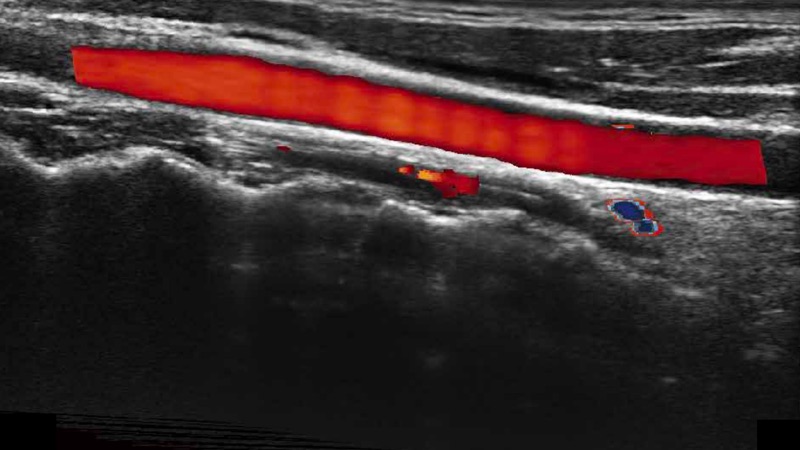

高分辨率血流成像技術提高了對低速血流信號的檢測能力。在提高空間分辨率的同時,也克服了血流外溢現(xiàn)象,為用戶提供更加真實的血流動力學信息。